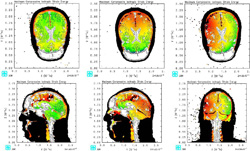

The 3-D simulations are visualized using two-dimensional multi-colored images of a man’s head that record an enormous amount of data. Taylor and Ford have focused on three types of energy entering the brain that may cause TBI: compressive isotropic energy associated with crushing; tensile isotropic energy that tends to expand parts of the brain and could lead to cavitation; and shear energy that causes distortion and tearing of soft tissue. The pressure and stress within the brain show up as colors moving in slow motion through and around the brain cavity on videos created from the simulations.

A battery of tests measured the subjects’ memory, language and intelligence. These results were correlated with changes in functional magnetic resonance imaging (fMRI) from the patients. The 3-D fMRI studies can detect and map networks in the brain used for processes like movement, vision and attention. By comparing this data with those of a control group, Ford identified a subgroup of networks displaying abnormal brain activity in the patients. These results were then compared with energy deposition maps predicted by the computer simulations.

The research showed that certain regions of patients’ brains are hyperactive, perhaps because they are compensating for adjacent, damaged areas of the brain that were hit with high energy from the blasts. The hyperactive regions are those that experienced the least shear and tensile energies, according to the computer simulations, which can be used to predict where the hyperactivity will likely occur, they say.